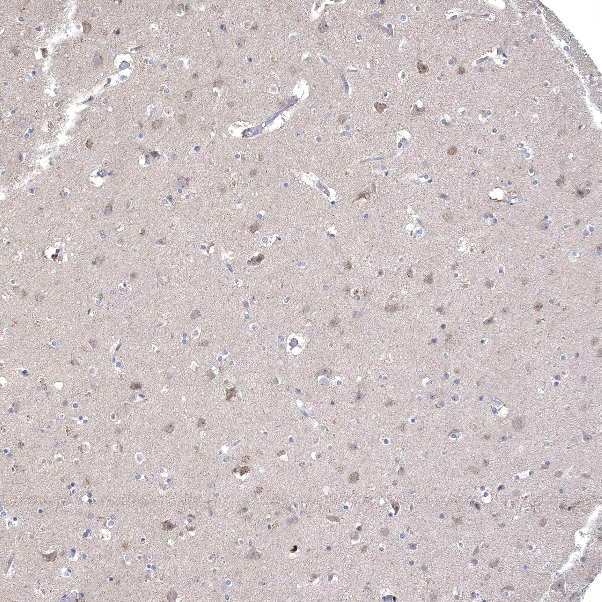

Immunohistochemical staining of human Cerebral cortex shows moderate cytoplasmic positivity in neuronal cells.